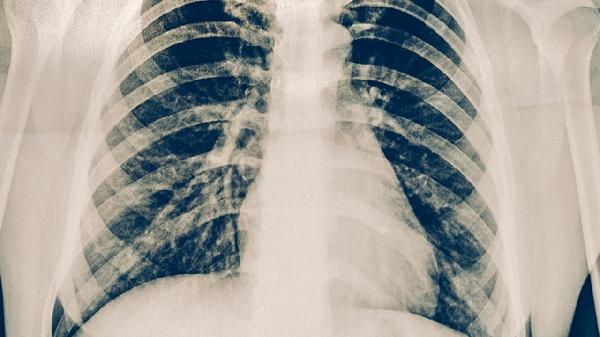

严重胸骨骨折可能出现骨折端移位、胸廓变形,甚至损伤后方的心脏、大血管或肺组织。这类患者需绝对卧床2-4周,保持平卧位减少骨折端移动,必要时采用镇痛药物如洛索洛芬钠片、塞来昔布胶囊缓解疼痛。合并血气胸者需行胸腔闭式引流术,严重移位骨折可能需手术内固定。卧床期间应每2小时协助翻身拍背,进行下肢踝泵运动预防血栓。

胸骨骨折恢复期应保持高蛋白饮食,适量补充维生素D和钙剂,如碳酸钙D3片。睡眠时可用枕头垫高背部缓解疼痛,避免侧卧压迫患处。3个月内禁止提重物及对抗性运动,定期复查CT评估骨痂形成情况。若出现突发胸痛、呼吸困难需立即就医。